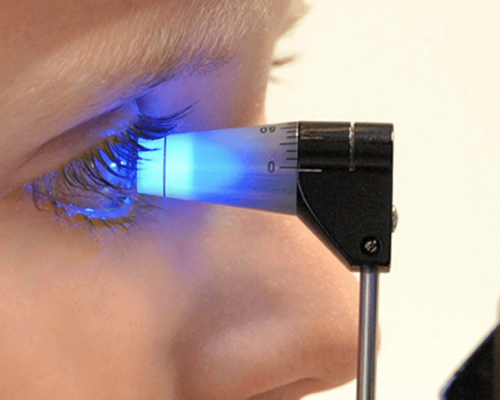

Médica Oftalmologista especialista no tratamento das doenças da retina

Mapeamento de Retina: um cuidado essencial para a saúde dos seus olhos

O mapeamento de retina é um exame fundamental para avaliar a saúde ocular de forma